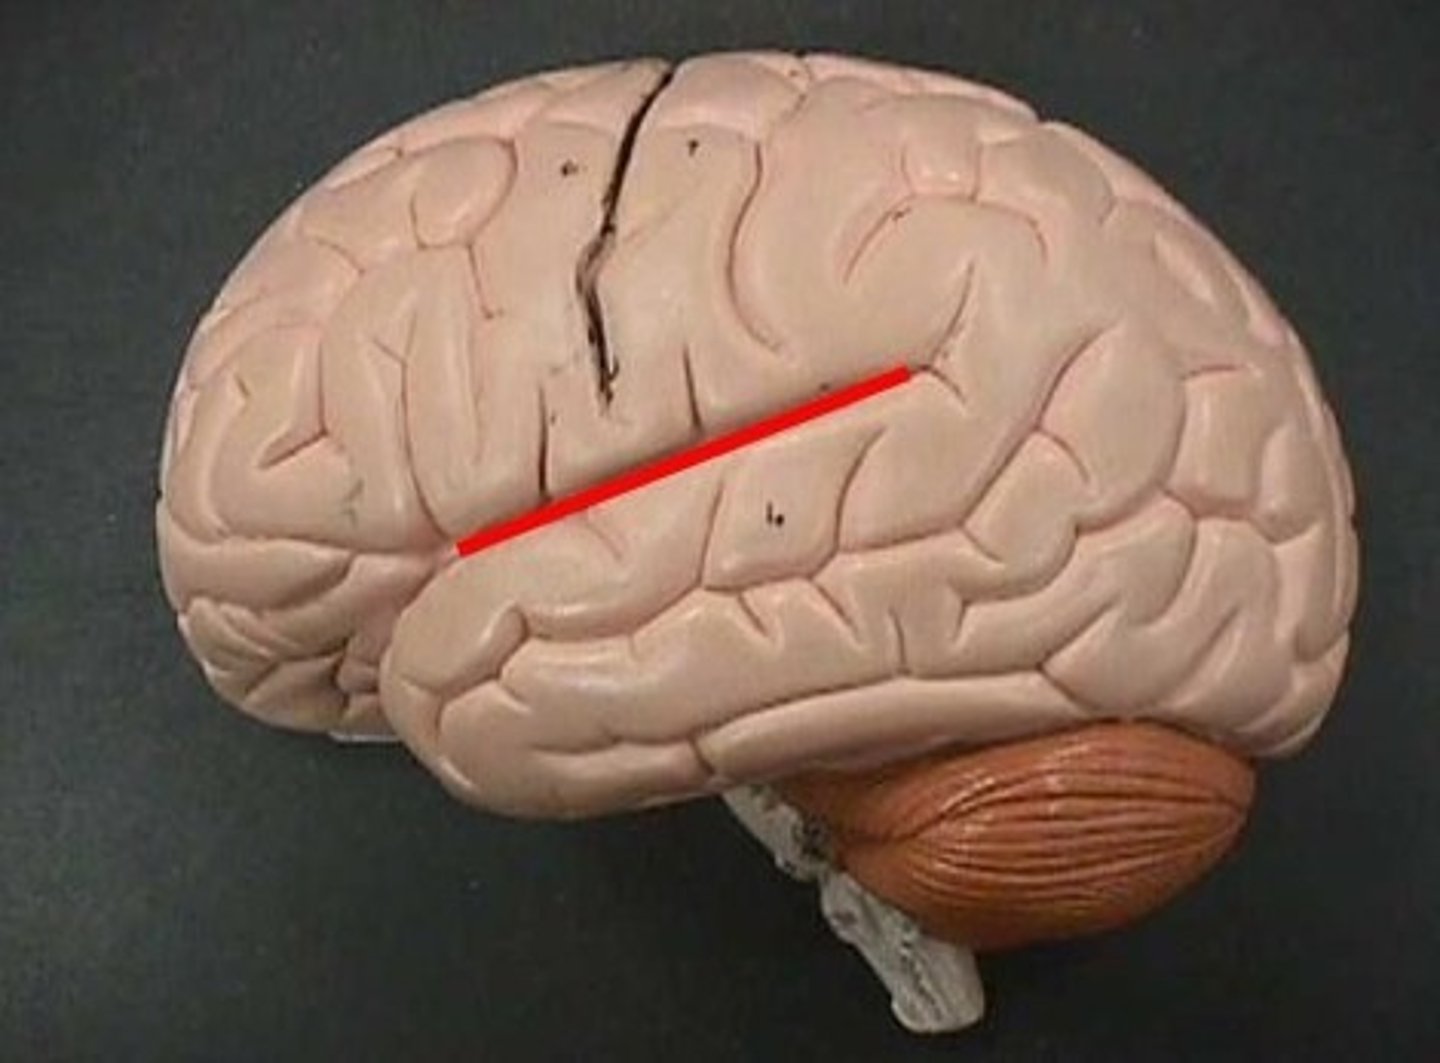

central sulcus

lateral sulcus

transverse fissure

precentral gyrus

postcentral gyrus

longitudinal fissure

frontal lobe

temporal lobe

parietal lobe

occipital lobe